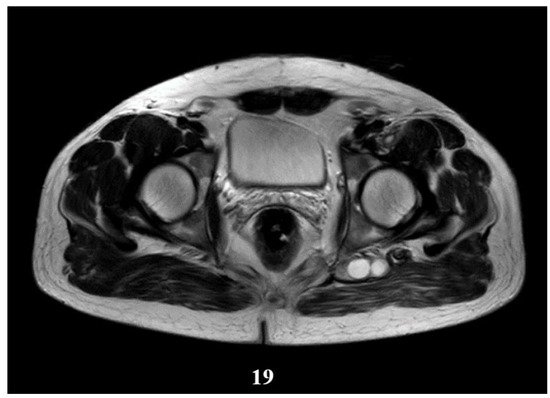

Figure 19.

T2W sequence, axial—Postoperative residual hydatid cyst located at the level of the left psoas muscle and deep to the left gluteus maximus muscle (part 1).

Deep from the gluteus maximus muscle on the left side, there are multiloculated, multiple septate intralesional, relatively well delimited areas, which seem to communicate both with each other and with lesions of a similar appearance located in the thickness and adjacent to the quadratus femoris muscle on the left side, with total dimensions in the coronal plane of approximately 11.3/6.4 cm, with the most likely appearance of parasitic cysts (Figure 19, Figure 20 and Figure 21).